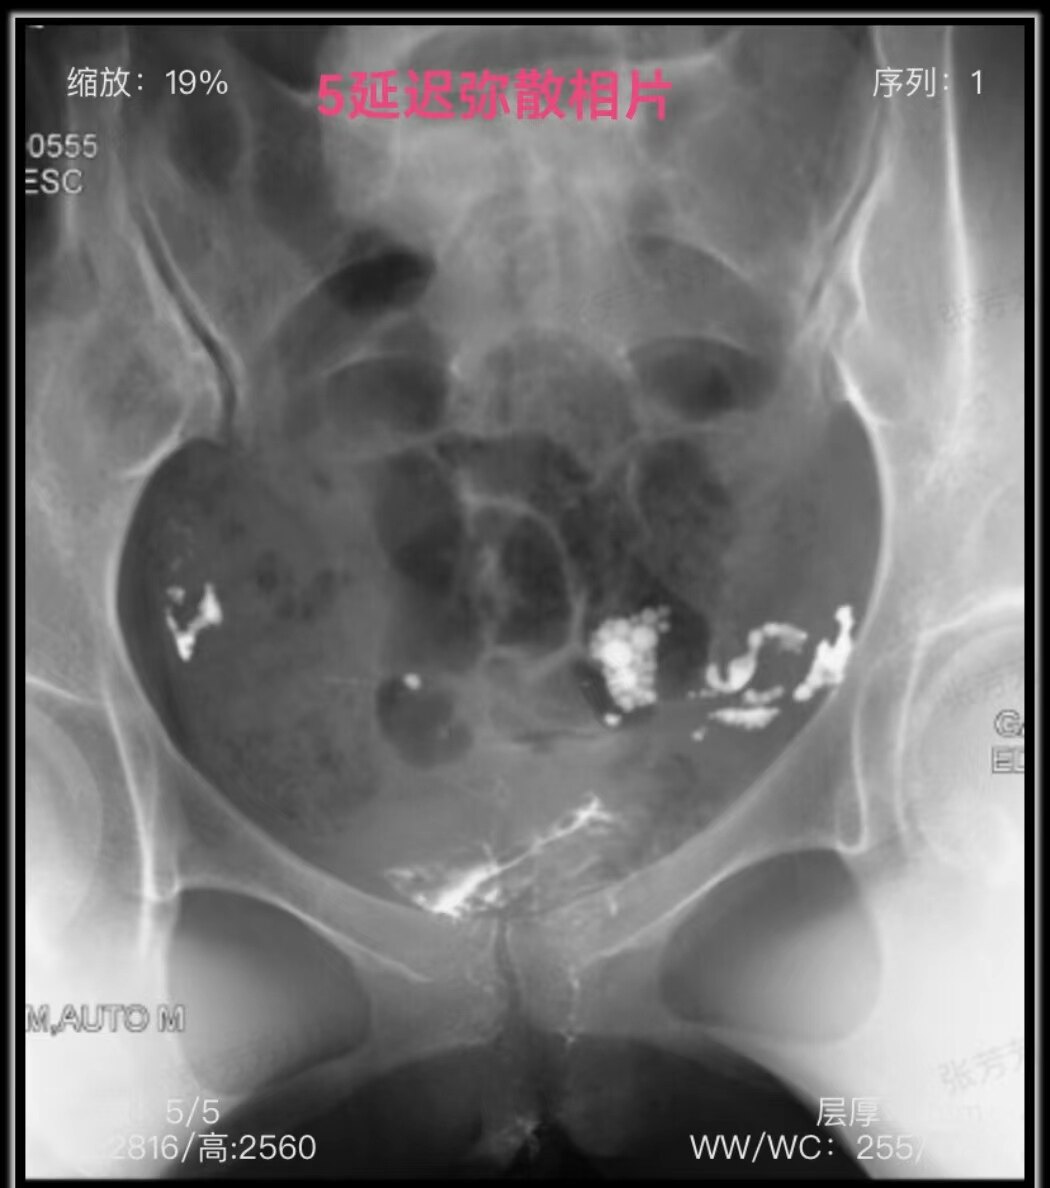

拔掉造影管2小时后延迟弥散相片:双侧输卵管伞部周围可见造影剂弥散,以左侧明显。因为盆腔有少量液体,碘油在盆腔左侧呈多小个圆形聚集在一起